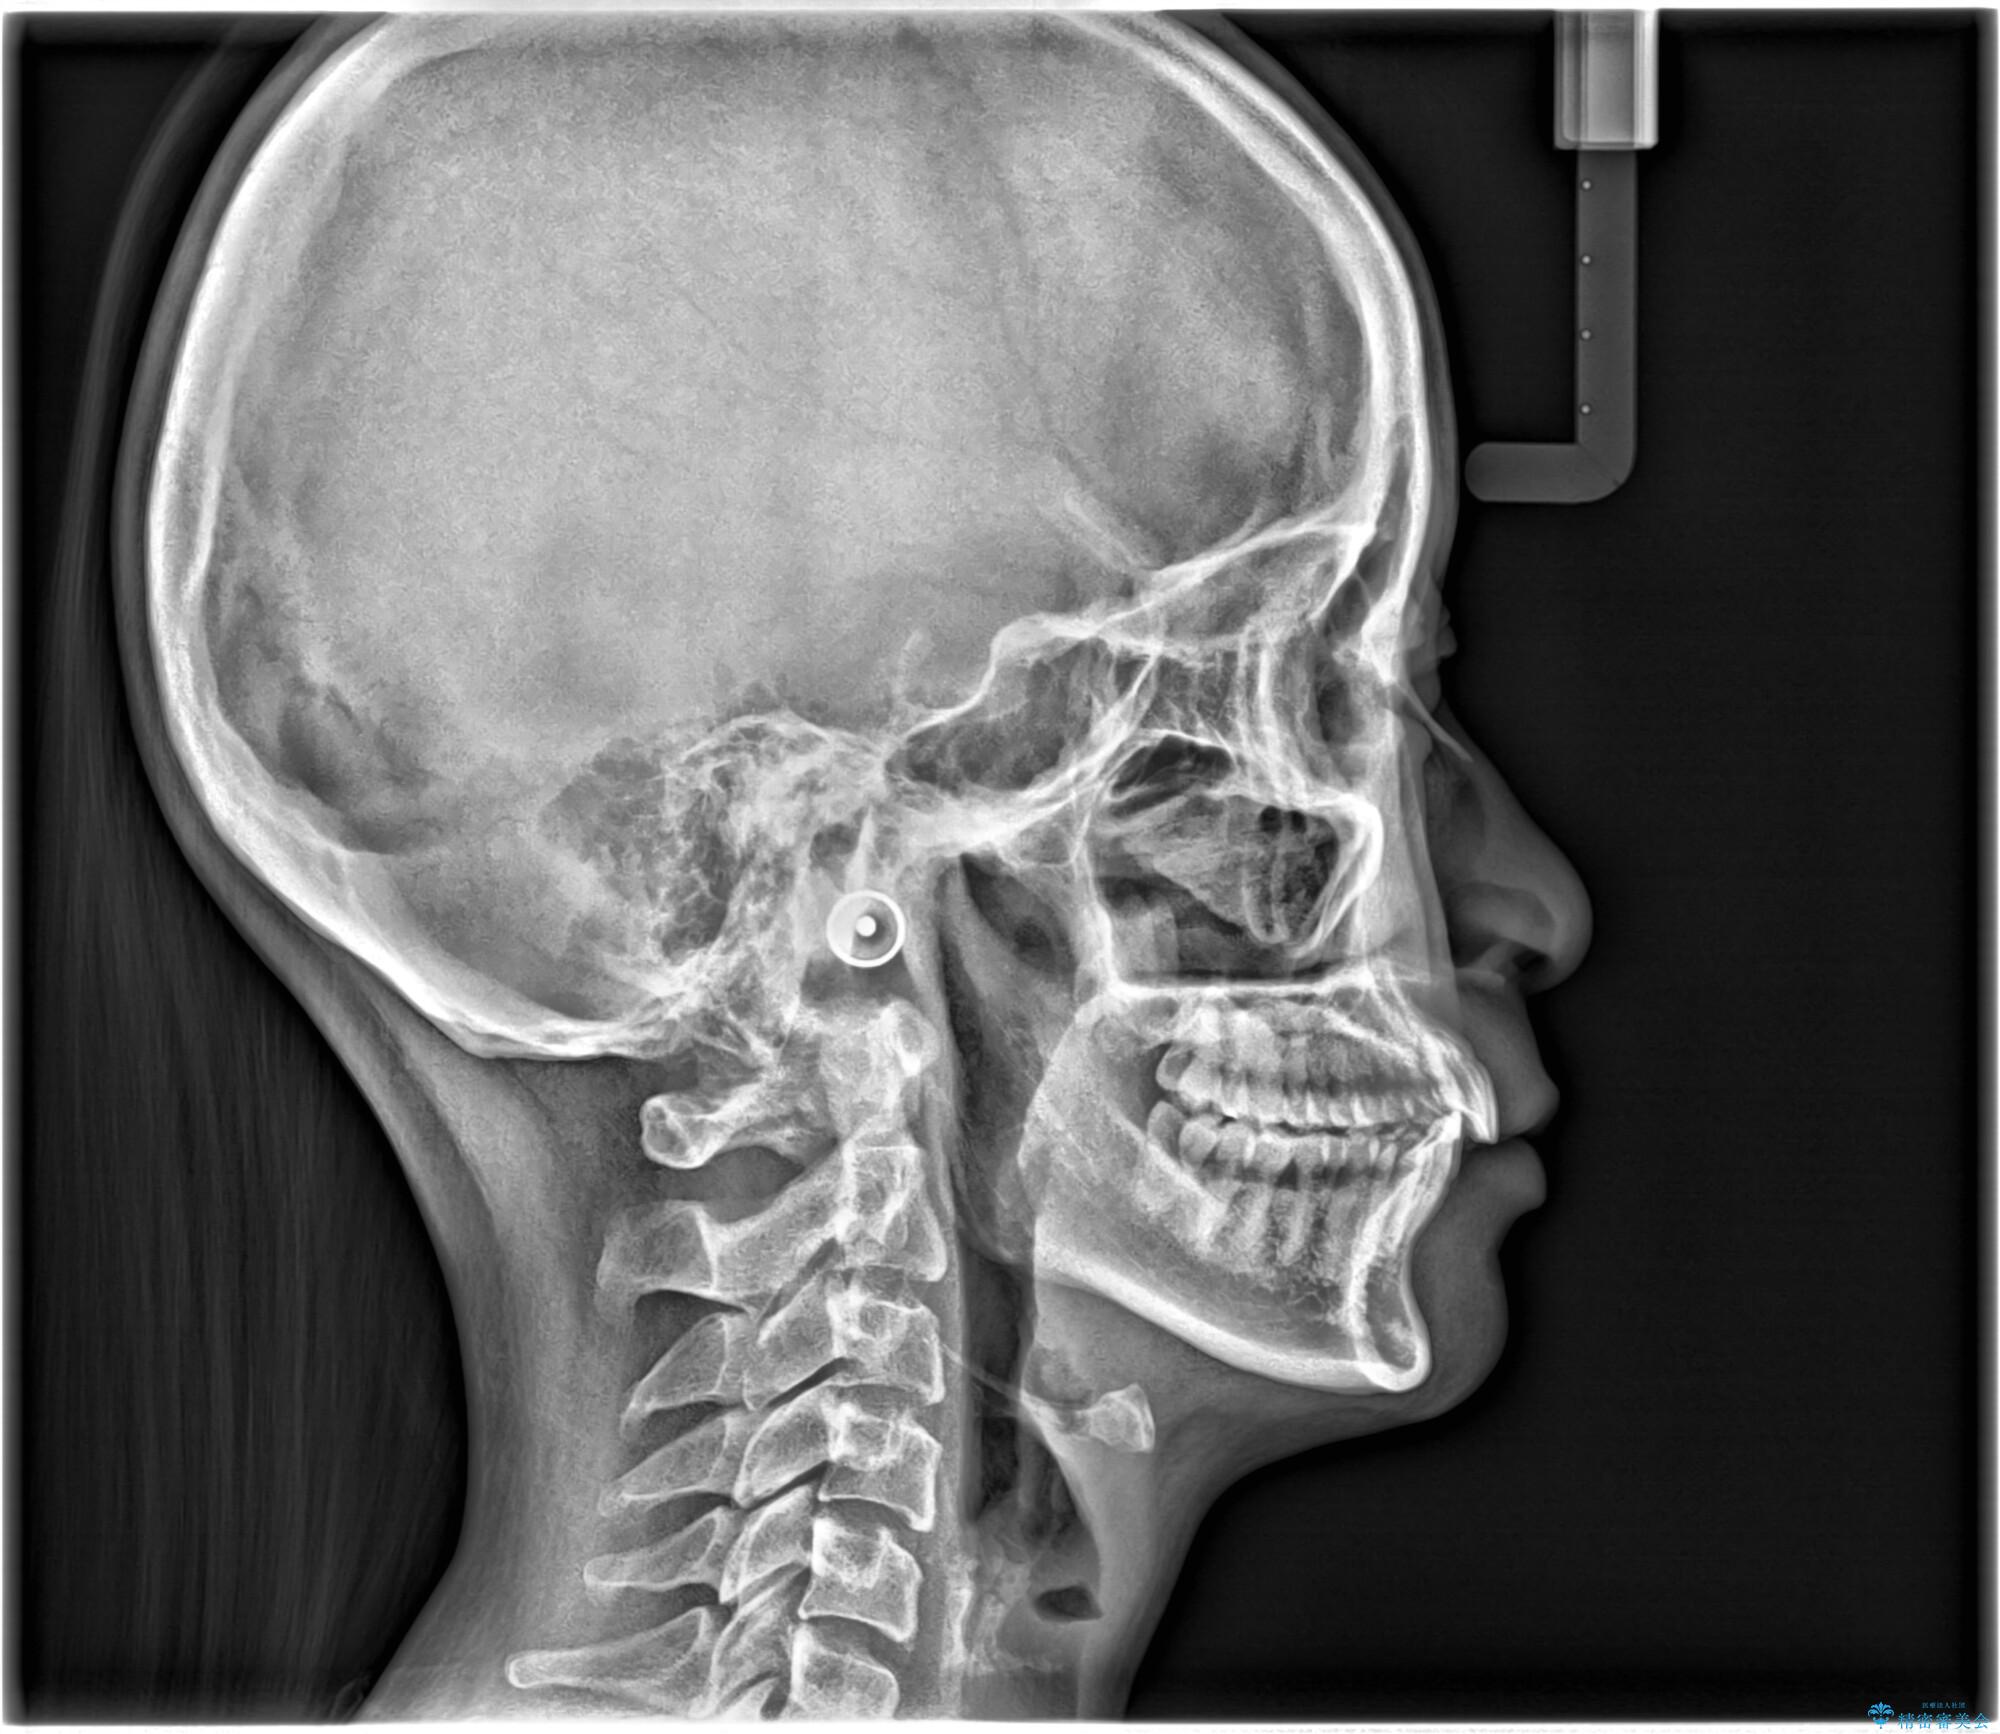

- 前歯が出ていることを主訴に来院されました。

下顎前歯が1本欠損していることもあり、前突はある程度残ることを説明し、インビザラインにて治療を行いました。

今回は抜歯矯正ではなく歯列弓の拡大とIPR、遠心移動を行って配列することができました。

口元も改善し患者さんには喜んでいただけました。

下顎前歯が1本少ないため、上下の正中は合いません。